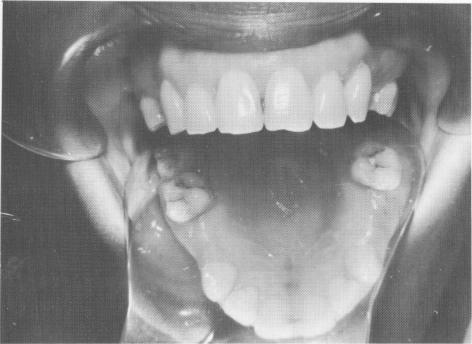

Fig. 8-9. Two bicuspids were missing bilaterally in an otherwise caries-free maxilla. Also, no previous fillings existed.

Here single tooth restorations were performed on a 32-year-old woman who was missing both maxillary bicuspid teeth on both sides of her arch (Fig. 8-9). Because her neighboring teeth had no fillings or decay, she did not want them prepared as abutments.

2 Bilateral missing bicuspids in caries-free maxilla, implant indication